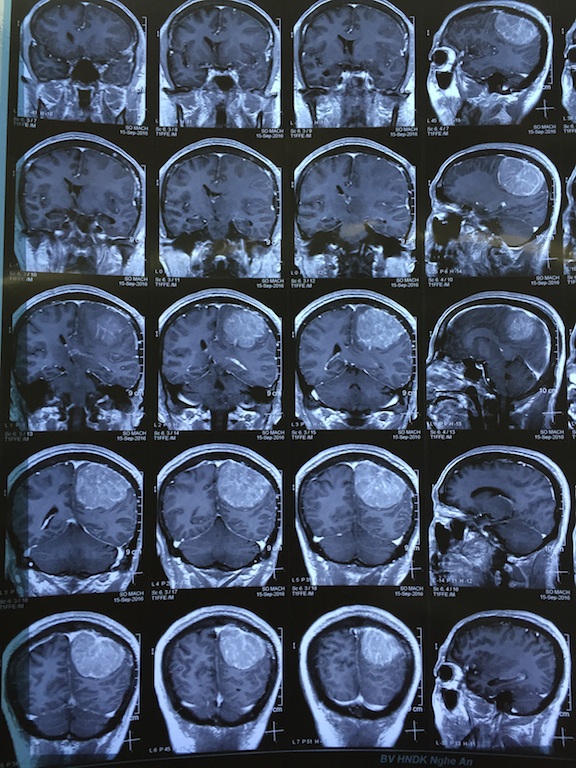

Qua hình ảnh chụp phim MRI, phát hiện hình ảnh khối choán chỗ lớn vùng đỉnh chẩm não sau, các bác sỹ xác định bệnh nhân Thường bị U màng não thể biểu mô độ 1.

Thạc sỹ Hoàng Kim Tuấn - Phó trưởng khoa Phẫu thuật thần kinh cột sống nhận định: “Khối u ở màng não của bệnh nhân Thường có kích thước lớn nhất từ trước tới nay chúng tôi từng gặp (6x7cm), chiếm 1/4 não bộ, chèn đẩy, đè ép nhiều phần não.

Khối u lại nằm ở vị trí bán cầu não ưu thế nên số lượng mạch máu đến nuôi nhiều. Chính vì vậy, việc dùng phương pháp can thiệp nút động mạch để cầm máu trước mổ cho những khối u não lớn đem lại hiệu quả cao.